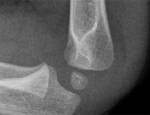

Radial head fractures

| stable | • isolated undisplaced or minimally displaced fracture • nearly always impacted, with intact periosteum, and are unlikely to displace. • Mx - conservative. Stiffness is the main adverse outcome and neither immobilisation or early mobilisation are necessarily superior |

| unstable | • usually associated with other bony or ligamentous injury • usually involve several detached, mobile fragments with little or no soft-tissue attachment • often associated with an elbow dislocation, proximal ulna fracture, or injury to the interosseous ligament of the forearm |